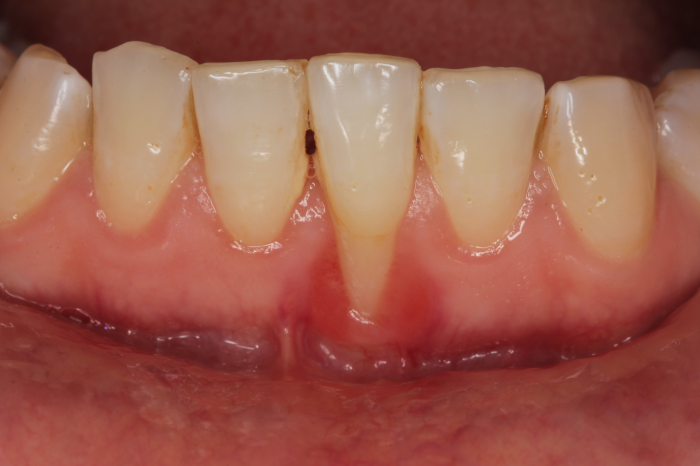

구내염이 생긴 위치에 약을 바르려고 거울로 구강내부를 확인해 보다가 문득 치아가 길어져 있는 것 같거나 잇몸내려앉음이 발생하여 뿌리가 밖으로 노출되어 있는 것 같다면, 치료를 해야 하는 건지, 만일 한다면 어디서 치료를 진행해야 하는지 그 과정은 어떻게 되는지 정보가 부족해 고민이 크실 것 같은데요. ...

구내염이 생긴 위치에 약을 바르려고

거울로 구강내부를 확인해 보다가

문득 치아가 길어져 있는 것 같거나

잇몸내려앉음이 발생하여 뿌리가

밖으로 노출되어 있는 것 같다면,

치료를 해야 하는 건지, 만일 한다면

어디서 치료를 진행해야 하는지

그 과정은 어떻게 되는지 정보가

부족해 고민이 크실 것 같은데요.

잇몸이 내려앉는 이유?

우리의 치아 구조는 겉면인 법랑질과

그 속의 상아질로 구성되어 있으며,

잇몸 속에 치주낭이라고 부르는

약 2mm의 작은 틈새가 존재했어요.

이러한 법랑질에는 구강 내

제대로 제거되지 않은 이물질을 먹고

자란 다양한 세균들과 침으로 이루어진

플라크라고 부르는 세균 막이

투명하고 얇게 씌워져 있는데요.

주기적으로 꼼꼼히 양치질을 해주어

위와 같은 플라크를 제거해 주어야

하지만, 제대로 제거해 주지 않는다면

이는 곧 치태가 되어 구강 내의

수많은 세균을 번식시키는 요인이 되고,

결국 치아와 잇몸 사이에 쌓이면서

딱딱하게 굳어 치석이 됩니다.